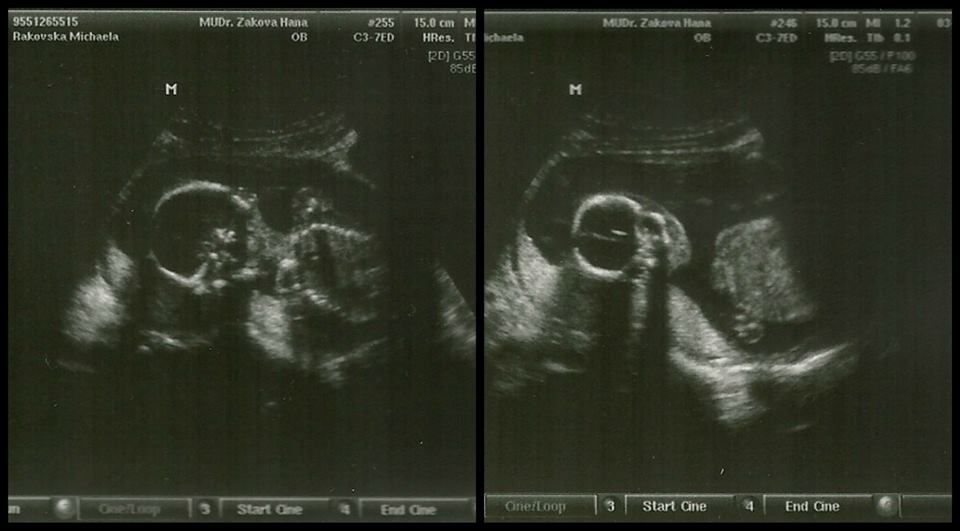

18+5tt a vážíme asi 280g, na kontrole jsme nebyly ani chvíli v klidu :P Jsem neposeda a už maminku kopu... Špatně se dívalo mezi nožky, ale pořád vypadáme na Laurinku, protože žádný camprlík tam nebyl vidět :P <3